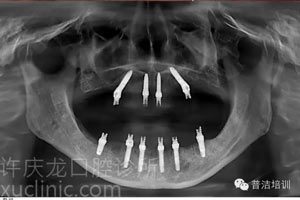

![]() | ![]() | |

植牙前口內照 | 植牙前CT圖 |